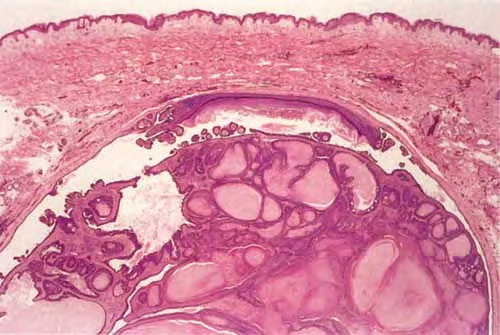

Hidradenoma papilliferum = الغدوم العرقي الحليمي